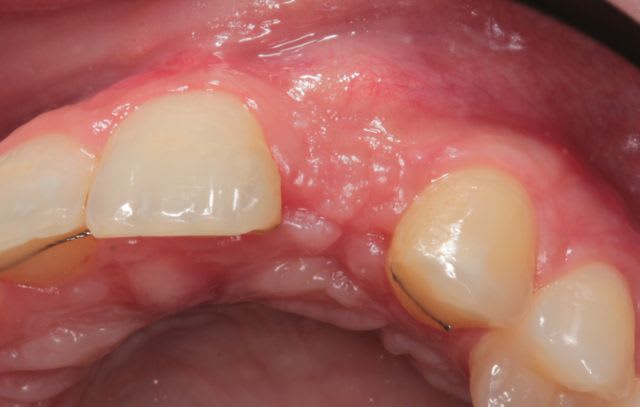

Je remonte le post pour faire la différence greffe onlay et 2D

et la suite des tofs